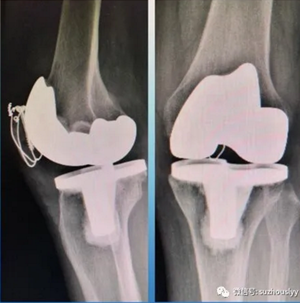

科主任刘长征带领团队主持术前讨论,副主任医师董新明、邵全安、许康永,主治医师王晟、年争好等医师对患者病例进行分析讨论,制定了各种治疗方案的可能并发症和应对措施后,在麻醉科的大力支持下,顺利完成一次手术解决髌骨骨折和膝关节骨性关节炎的治疗 — 即一期行膝关节置换+髌骨骨折复位内固定术。术后功能恢复良好,活动自如,这也更加坚定了患者自身通过康复训练就能恢复正常行走的信心,避免了致残风险。患者及其家属感到非常满意。

术后膝关节正侧位

术后复查行走屈膝功能满意